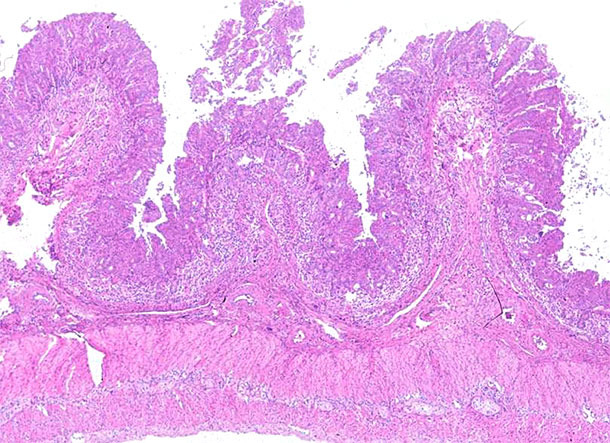

Il convient de souligner que l’on trouvait fréquemment les problèmes entériques dans les élevages affectés par le PCV2-SD. Cependant, le mécanisme exact par lequel ces animaux malades avaient de la diarrhée n’était pas clair. D’une part, l’immunosuppression systémique liée au PCV2-SD serait l’une des raisons principales pour déclencher l’effet des pathogènes entériques existants dans l’élevage, qui peuvent ne pas s’exprimer à moins que le système immunitaire soit compromis. D’autre part, le résultat pathologique du PCV-SD sur une partie des animaux comprend un niveau variable d’entérite granulomateuse (photos 1 et 2) qui entraînerait de la diarrhée due à l’altération de la perméabilité de la barrière intestinale. Dans ce scénario, l’arrivée des vaccins PCV2 a entraîné à une diminution radicale des porcs et des élevages qui présentaient des signes cliniques et des lésions de PCV2-SD et, par conséquent, la concomitance de l’infection virale avec d’autres pathogènes entérique a significativement diminué.

Photo 1 : Iléon. Déplétion marquée des lymphocytes et inflammation granulomateuse des plaques de Peyer dans l’iléon d’un porc atteint par la maladie systémique associée au PCV2. Coloration à l’hématoxyline et à l’éosine.